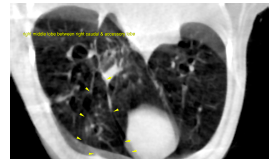

CT of the thorax, plain and post contrast- The main bronchus of the right middle lobe emerges in a ventral direction from the

bifurcation. The bronchus is dilated with an abrupt ending and collapsed lumen 5 mm

after its origin. There is regional lobar opacification and volume loss at this level. Air

filled bronchi are recognized few centimeters distal to the abrupt collapse again. The

distal portion of the right middle lobe is aerated but reveals low volume and is

displaced caudally between the right caudal and accessory lung lobes.

There is moderate bilaterally symmetric pleural effusion.